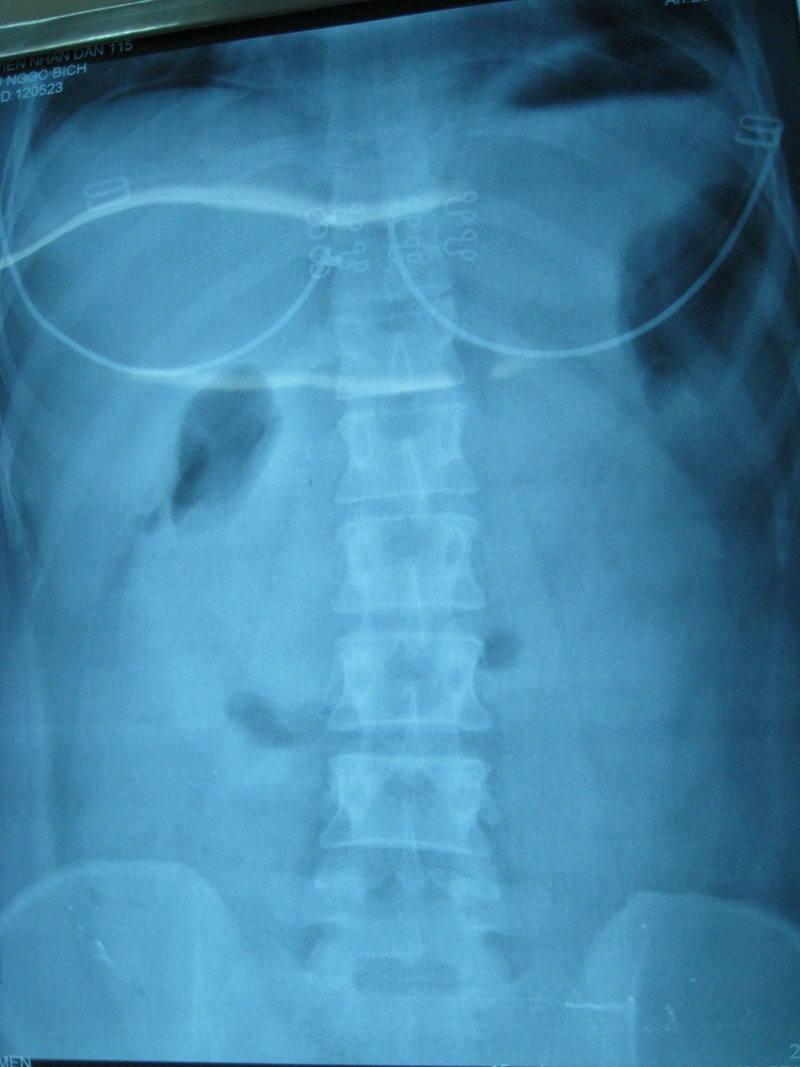

Phương pháp này rất phổ biến để xác định thủng tạng rỗng, thường được sử dụng trong các trường hợp cấp cứu. Người bệnh sẽ được hướng dẫn chụp X-quang bụng ở tư thế đứng hoặc nửa nằm nửa ngồi để phát hiện hơi bên dưới cơ hoành.